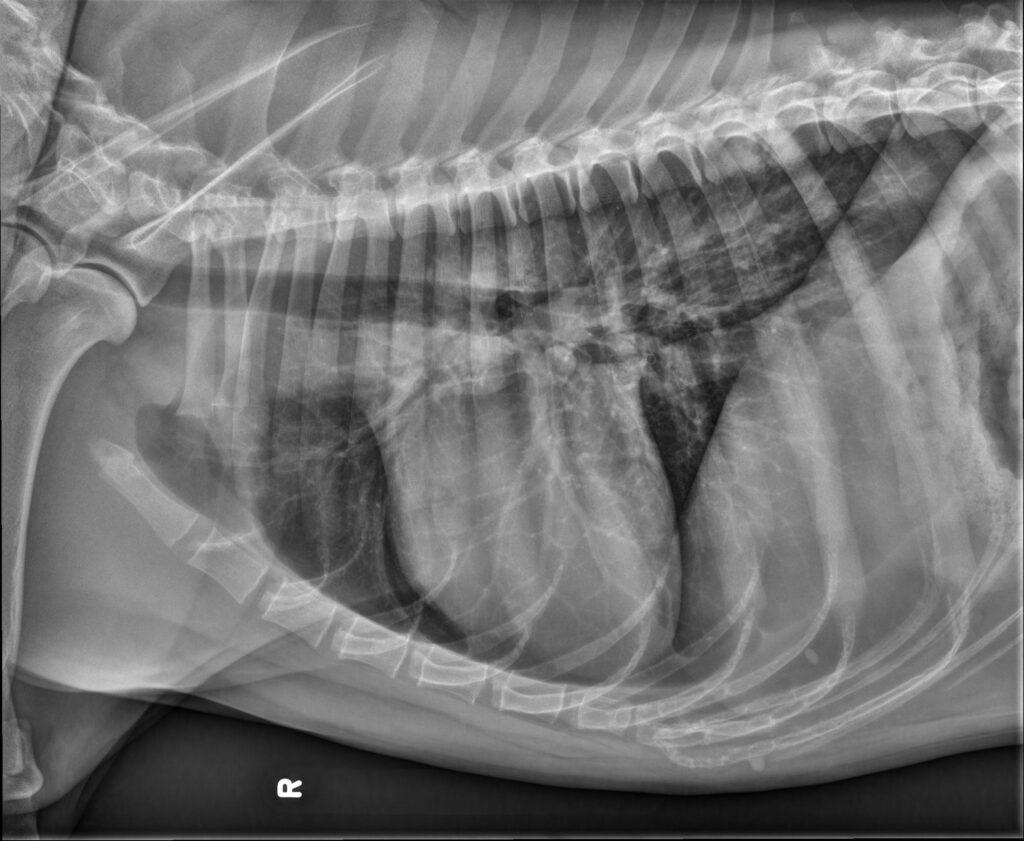

Radiology Quiz October 2025

History 12 year old boxer. Weight loss, hyporexia, lethargy.

...